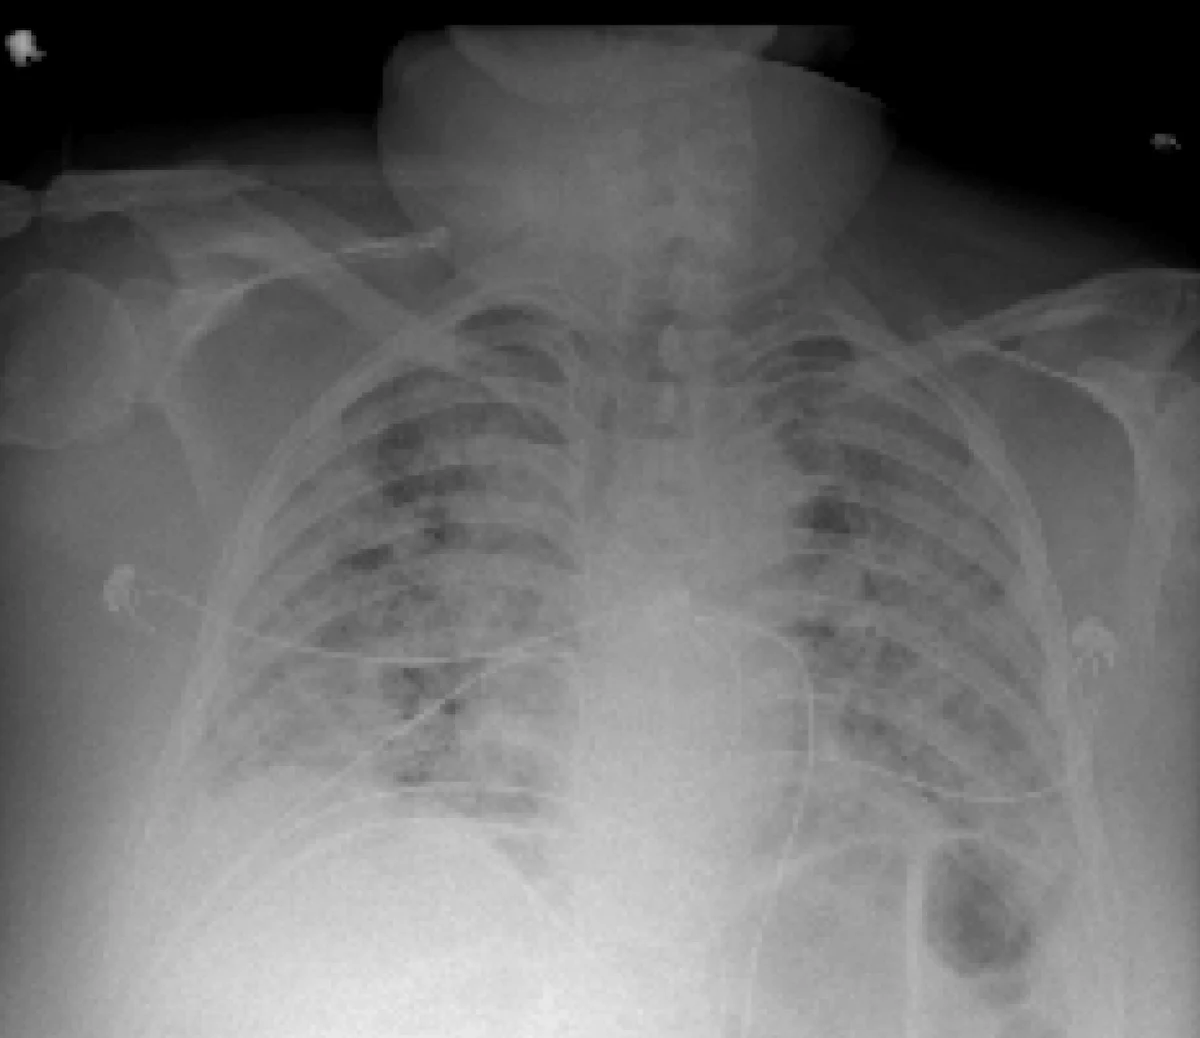

Program komputerowy, wykorzystujący sztuczną inteligencje może na podstawie zdjęć rentgenowskich płuc z dużą dokładnością przewidywać, którzy pacjenci chodzy na Covid-19 są zagrożeni silnym pogorszeniem stanu zdrowia. Wyniki badań, opisane na stronie internetowej czasopisma "NPJ Digital Medicine" przez naukowców z New York University Grossman School of Medicine potwierdzają, że skuteczność przewidywania, u których pacjentów mogą pojawić się w ciągu czterech dni zagrażające życiu powikłania, sięga 80 procent.

Opracowany przez ekspertów NYU Grossman School of Medicine program wykorzystał do procesu uczenia się dane z 5224 zdjęć rentgenowskich klatki piersiowej, wykonanych u 2943 poważnie chorych na Covid-19 pacjentów. Do komputera wprowadzono też dane dotyczące wieku, rasy, wagi i płci pacjentów, wyniki ich badań laboratoryjnych, pomiarów temperatury i badań poziomu przeciwciał, a także dane dotyczące ich pobytu w szpitalu, potrzeby wykorzystania respiratora i ostatecznego wyniku terapii. 2405 z tych osób przeżyło, a z powodu Covid-19 zmarło 538.

Oprogramowanie wykorzystano potem do analizy 770 zdjęć rentgenowskich klatki piersiowej 718 innych pacjentów z Covid-19, przyjętych do szpitali NYU Langone w okresie od 3 marca do 28 czerwca 2020 roku. W 4 na 5 przypadków program skutecznie przewidział, którzy z tych pacjentów w ciągu 4 dni od hospitalizacji wymagali przeniesienia na oddział intensywnej terapii, podłączenia do respiratora, ewentualnie zmarli.